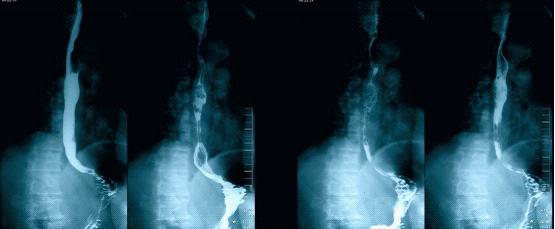

上消化道造影(双重):食管中段类圆形充盈缺损,考虑肿瘤性病变,可能来自食管黏膜下肌层;慢性胃炎;十二指肠升段憩室(图3)

图3